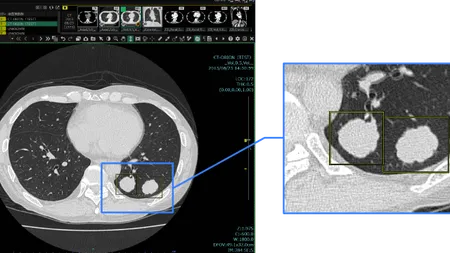

Plus.Lung.Nodule (CT-AI)は胸部CT画像に関心領域を表示し、肺結節やリンパ節等の視認性向上を図るプログラム医療機器です。

胸部CT画像から「関心領域」を抽出

胸部CT画像から肺結節の候補を検出して表示する機能です。医師が再確認することで、見落しを低減します。